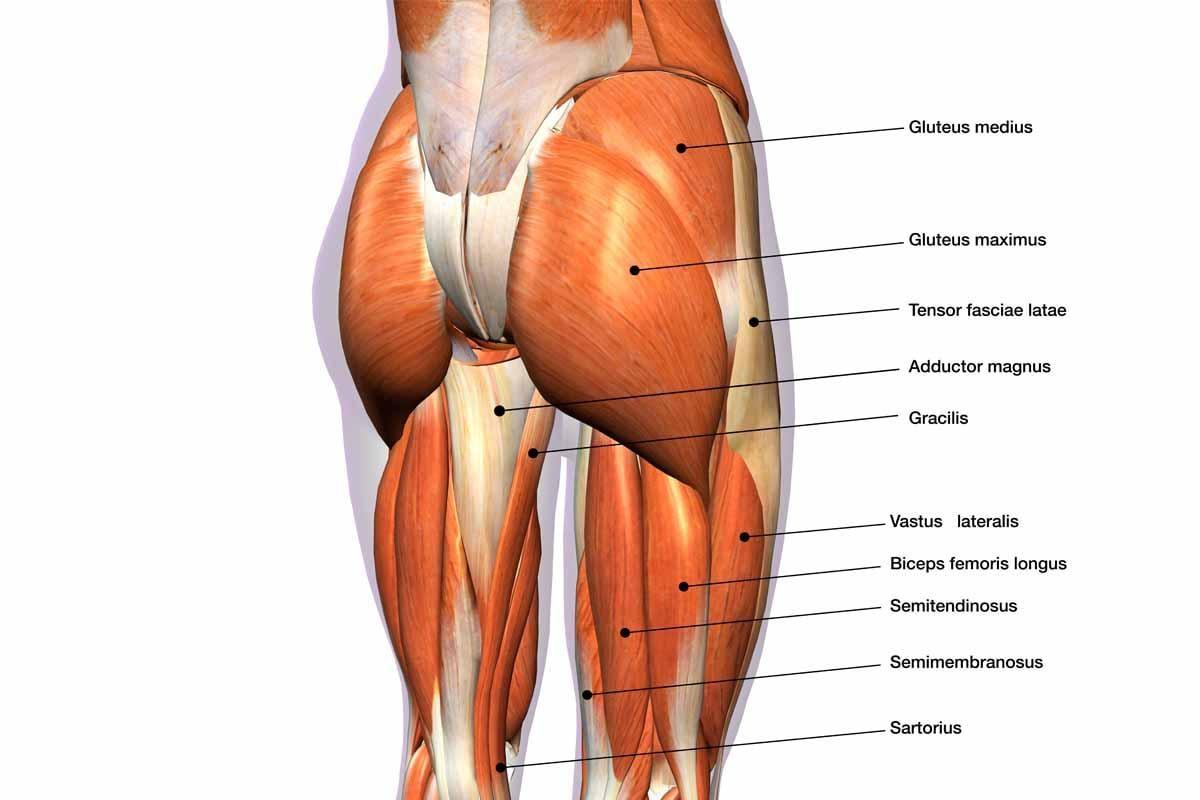

強化臀部肌肉

而與肌肉相關的腰骨痛,則很多時因為某些肌肉過於繃緊,另一些肌肉太弱而導致。例如工作太長時間維持坐姿,臀部肌肉就會經常處於放鬆狀態而變弱,當需要用到臀部肌肉時,簡單如行走、上樓梯、跑步等,就會尋求附近的肌肉幫忙,例如腰部的肌肉。

然而脊椎兩旁的肌肉本來屬核心肌群的一部分,用於穩定脊椎,只提供小範圍的旋轉和屈曲,並不能補足臀部肌力太弱的問題,因此久而久之就會過度繃緊、疼痛。所以只要解決臀部太弱的問題,就可解決腰骨痛。

我們可以做「直腿後擺」這個動作來強化臀部。在健身室當然可用專屬的器械或者健身椅來完成,而在家也可以借助床的邊緣做到此運動。這動作的重點是要由臀部肌肉帶動提起下半身,並做好每一次的動作,目標是10至12次,每日30秒便可。當然有時間可多做幾組。

此動作可重點強化臀部肌肉,每日30秒可助解決腰痛問題。